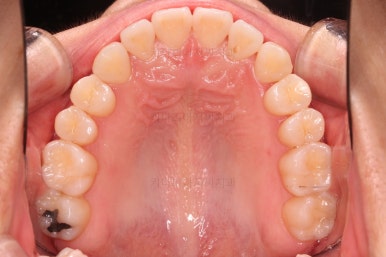

삐뚤한 덧니를 가지런하게 하기 위해서 필요한 부분의 어금니를 순차적으로 뒤로 밀어줍니다.

자세히 보면 치아 사이사이에 틈새가 생기는게 보이죠?

틈새를 일부러 만들어 해당 공간으로 덧니를 가지런하게 하는 원리입니다.

장치를 사용한지 1년 2개월째 사진입니다.

매우 가지런해졌죠.

보통 부산인비절라인은 풀세트로 3회가량 하게 되는데요.

이번 환자분은 1회로도 이 정도의 결과를 만들어 냈습니다.

이 정도의 느낌도 나쁘지는 않지만 미세하게 수정할 부분들이 보여 1회 더 제작하기로 했습니다.